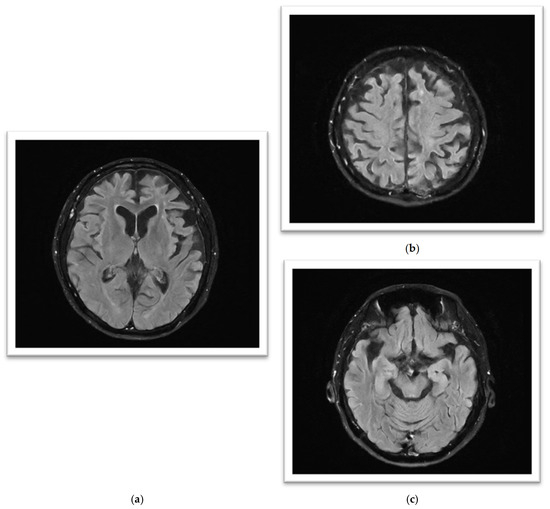

The initial brain MRI conducted in March 2023 demonstrated global cerebral involution with equivocal frontoparietal predilection and relative medical temporal lobe sparing. Global cortical atrophy (GCA) grade 1–2 was reported, showing mild to moderate brain atrophy with a reduced gyri volume, increased sulci and moderate ventricular dilatation [5]. There was evidence of progressive neurodegenerative changes in the brain MRI findings one year later; the second brain MRI in April 2024 showed predominant bilateral frontal and parietal volume loss, sparing the occipital and temporal lobes. A medial temporal lobe atrophy score (MTA) of grade 1 was reported (Figure 2). Amyloid positron emission tomography (PET) (Figure 3) confirmed the presence of amyloids, a hallmark of Alzheimer’s disease. While a lumbar puncture to measure cerebrospinal fluid (CSF) biomarkers (Aβ1-42 and tau) was offered, the family declined due to the invasive nature of the procedure.

Figure 2.

(a–c): MRI FLAIR sequence (from left to right): (a) significant symmetrical gyral thinning in frontal and parietal lobes; (b) significant symmetrical gyral thinning in frontal lobes, mostly sparing the occipital lobes; (c) reasonably preserved hippocampal volumes bilaterally.